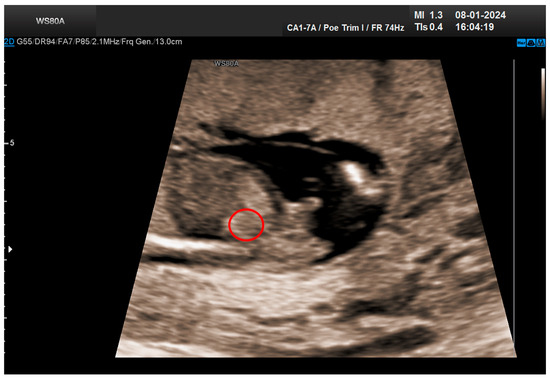

The combined test result indicated a low risk for trisomies, preeclampsia, and intrauterine growth restriction. However, during the ultrasound examination, the absence of the right renal tissue in the right parasagittal sections was noted (Figure 1). Examination of the embryo in axial sections demonstrated the presence of a relatively well-defined acoustically heterogeneous echogenic mass situated anterior to the spine, in sonographic contact with the renal tissue image correctly occupying the left lumbar fossa (Figure 2). Those aspects suggested the existence of a renal anomaly of crossed fused renal ectopia. No other embryonic anomalies were detected, the bladder image was present, and the amniotic fluid volume was normal. The calculated gestational age corresponded to the ultrasound estimate. The suspicion of crossed fused renal ectopia was maintained during a subsequent reevaluation at 17 weeks of pregnancy (Figure 3 and Figure 4).

Figure 1. Empty right renal fossa (circled in red)—first-trimester morphology scan at 13 weeks and 2 days.